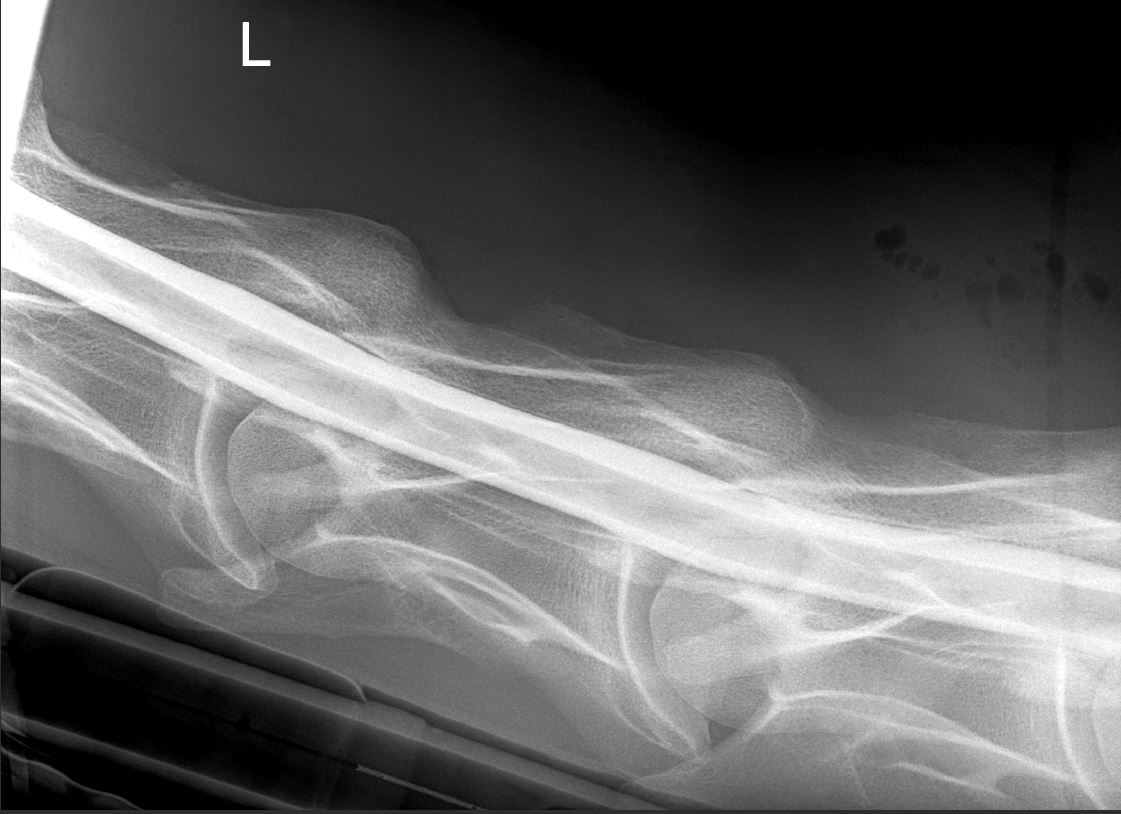

- Digital Radiography

- Fluoroscopy

- Neurologic Imaging. At CRES was routine perform neck radiography including oblique views and myelography. When needed, we have access to brain MRI.